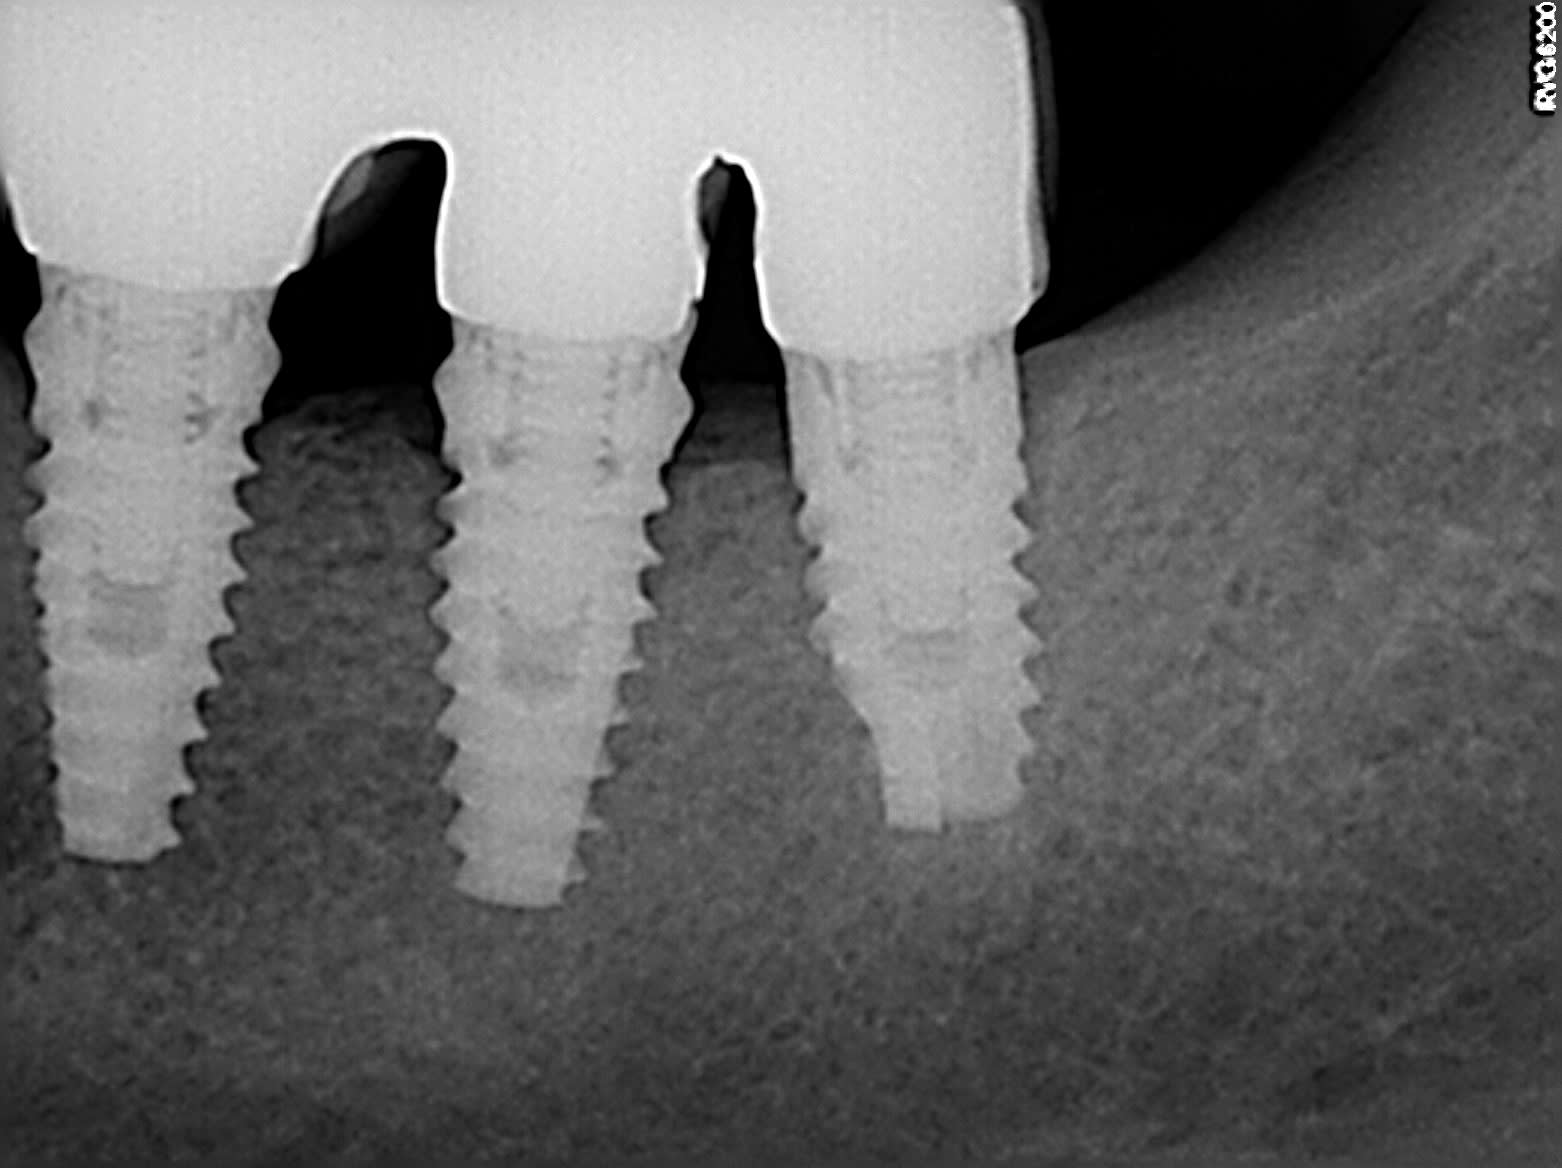

Quel qu un peut il me donner la marque de ces implants?

après, comme çà ils ont une bonne tête de biohorizon...

ouaip, çà m'a bien l'air d'être des biohorizon